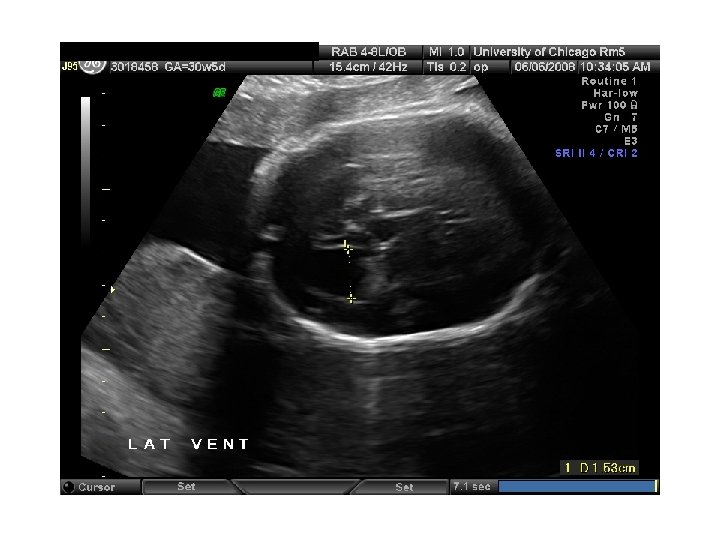

QUIZ What is Your Diagnosis? Case: Patient J. F. 30 years old, at 32 week gestation. Presented with the following pictures.

Answer: a) Trisomy 21 b) Non-immune Hydops c) Paravo virus Infection